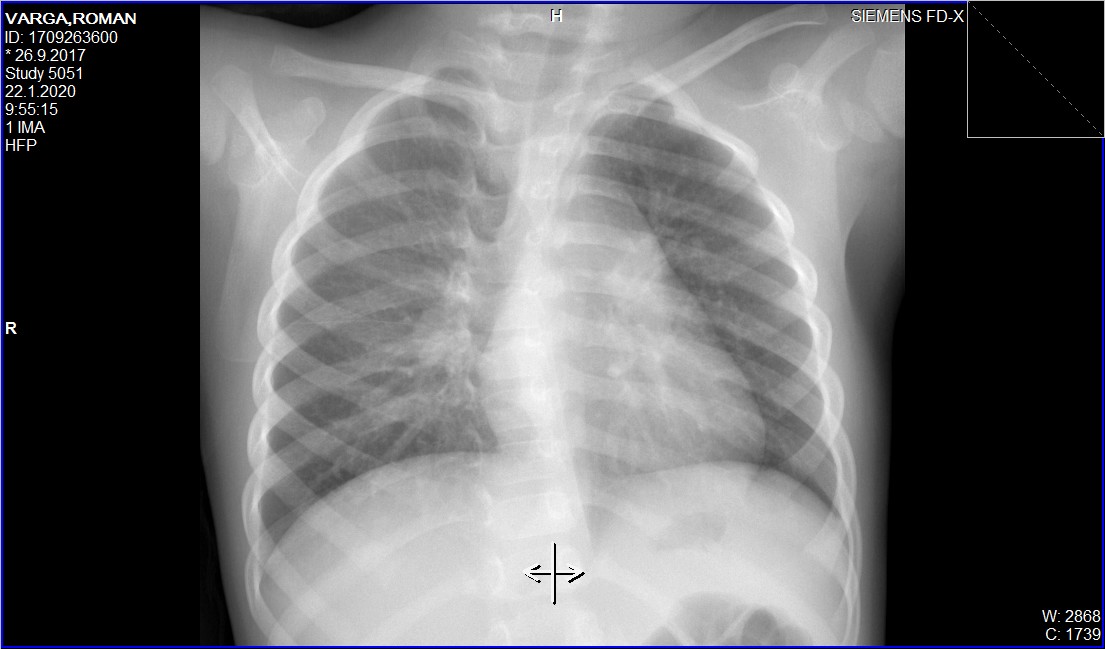

vpravo je v prieduške zmnožená bronchovaskulárna kresba, ktorá by sa vzhľadom k pozitívnemu klinickému obrazu a ťažkostiam dala hodnotiť ako bronchopneumonia vpravo.

To nie je úplne zápal pľúc, je to kombinovaný zápal priedušky a takým možným prechodom do zápalu pľúc.